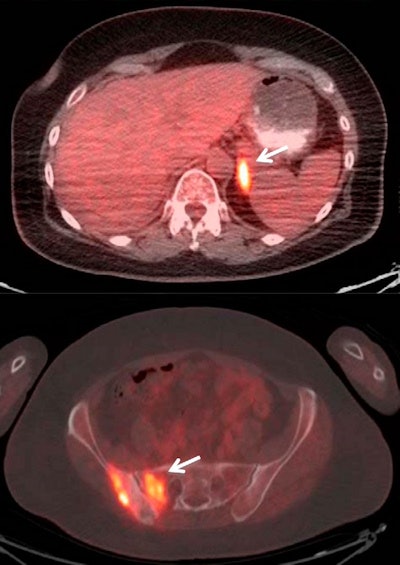

Of the 285 PET/CT scans, 149 (52%) were positive and 136 (48%) were negative for recurrence or metastasis, the researchers found.

The majority (219, or 77%) of the scans were conducted as routine follow-up without clinical suspicion of recurrent disease or metastasis. FDG-PET/CT identified recurrence or metastasis of lung cancer in 97 scans (44%) with no prior clinical suspicion, and it ruled out recurrence or metastasis in 16 scans (24%) conducted with prior clinical suspicion.